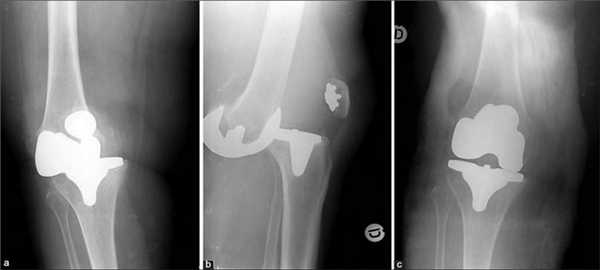

Рентген после операции. Протез стоит корректно.

У пациента отмечалась варусная деформация коленного сустава (О-образное искривление ног). Ходил с помощью трости, хромал на левую ногу. Левый коленный сустав сгибался на 110° и разгибался на 160°, в крайних положениях пациент чувствовал боль. При движении колено хрустело, но фронтальная плоскость оставалась стабильной, поэтому мужчина мог опираться на ногу.

При ощупывании левого коленного сустава в области возвратного нерва определялось небольшое количество жидкости, пациент отметил боль в середине колена.